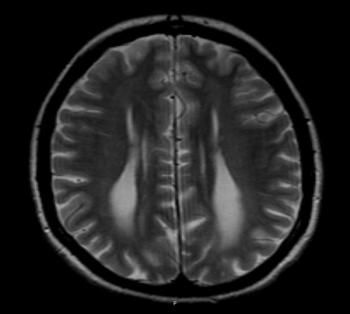

A 39 year-old female with Turner Syndrome completely asymptomatic in the previous years, presented to our department with recent onset of dizziness and fatigue.